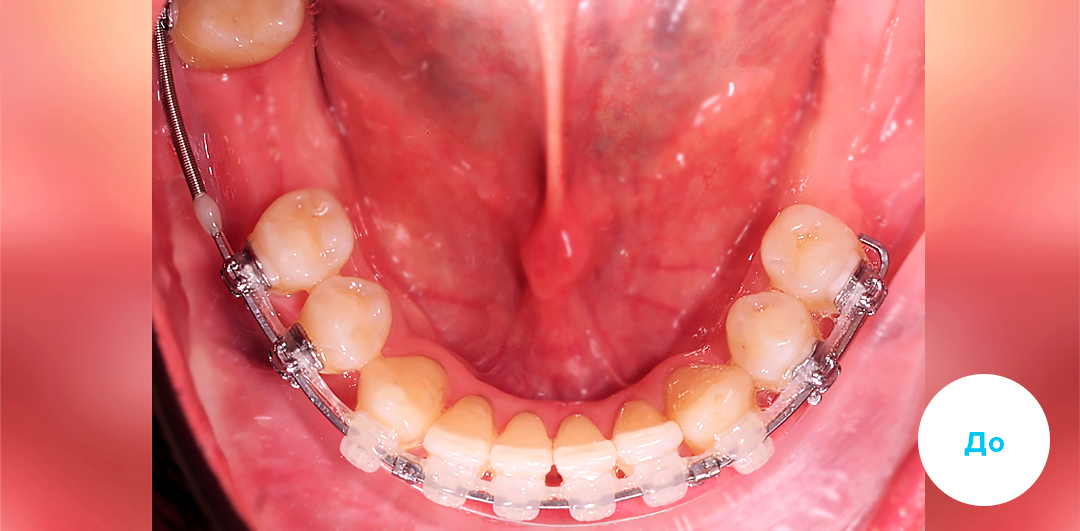

До

После

ИМПЛАНТАЦИЯ 3 ЗУБОВ С ПРЕДВАРИТЕЛЬНОЙ ОРТОДОНТИЧЕСКОЙ ПОДГОТОВКОЙ

Смотреть кейс